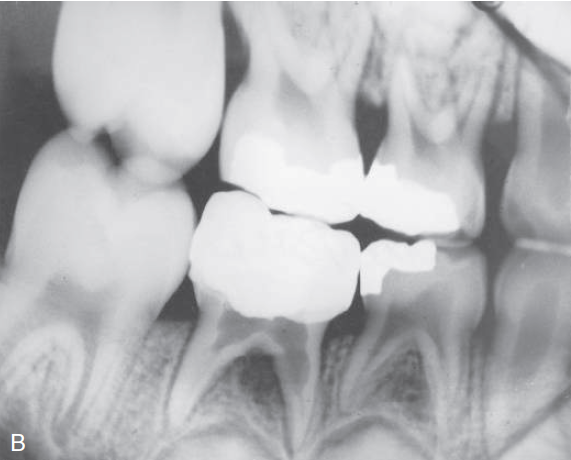

8. (Select ONE OR MORE correct answers)

Tooth 8.4 shows evidence of